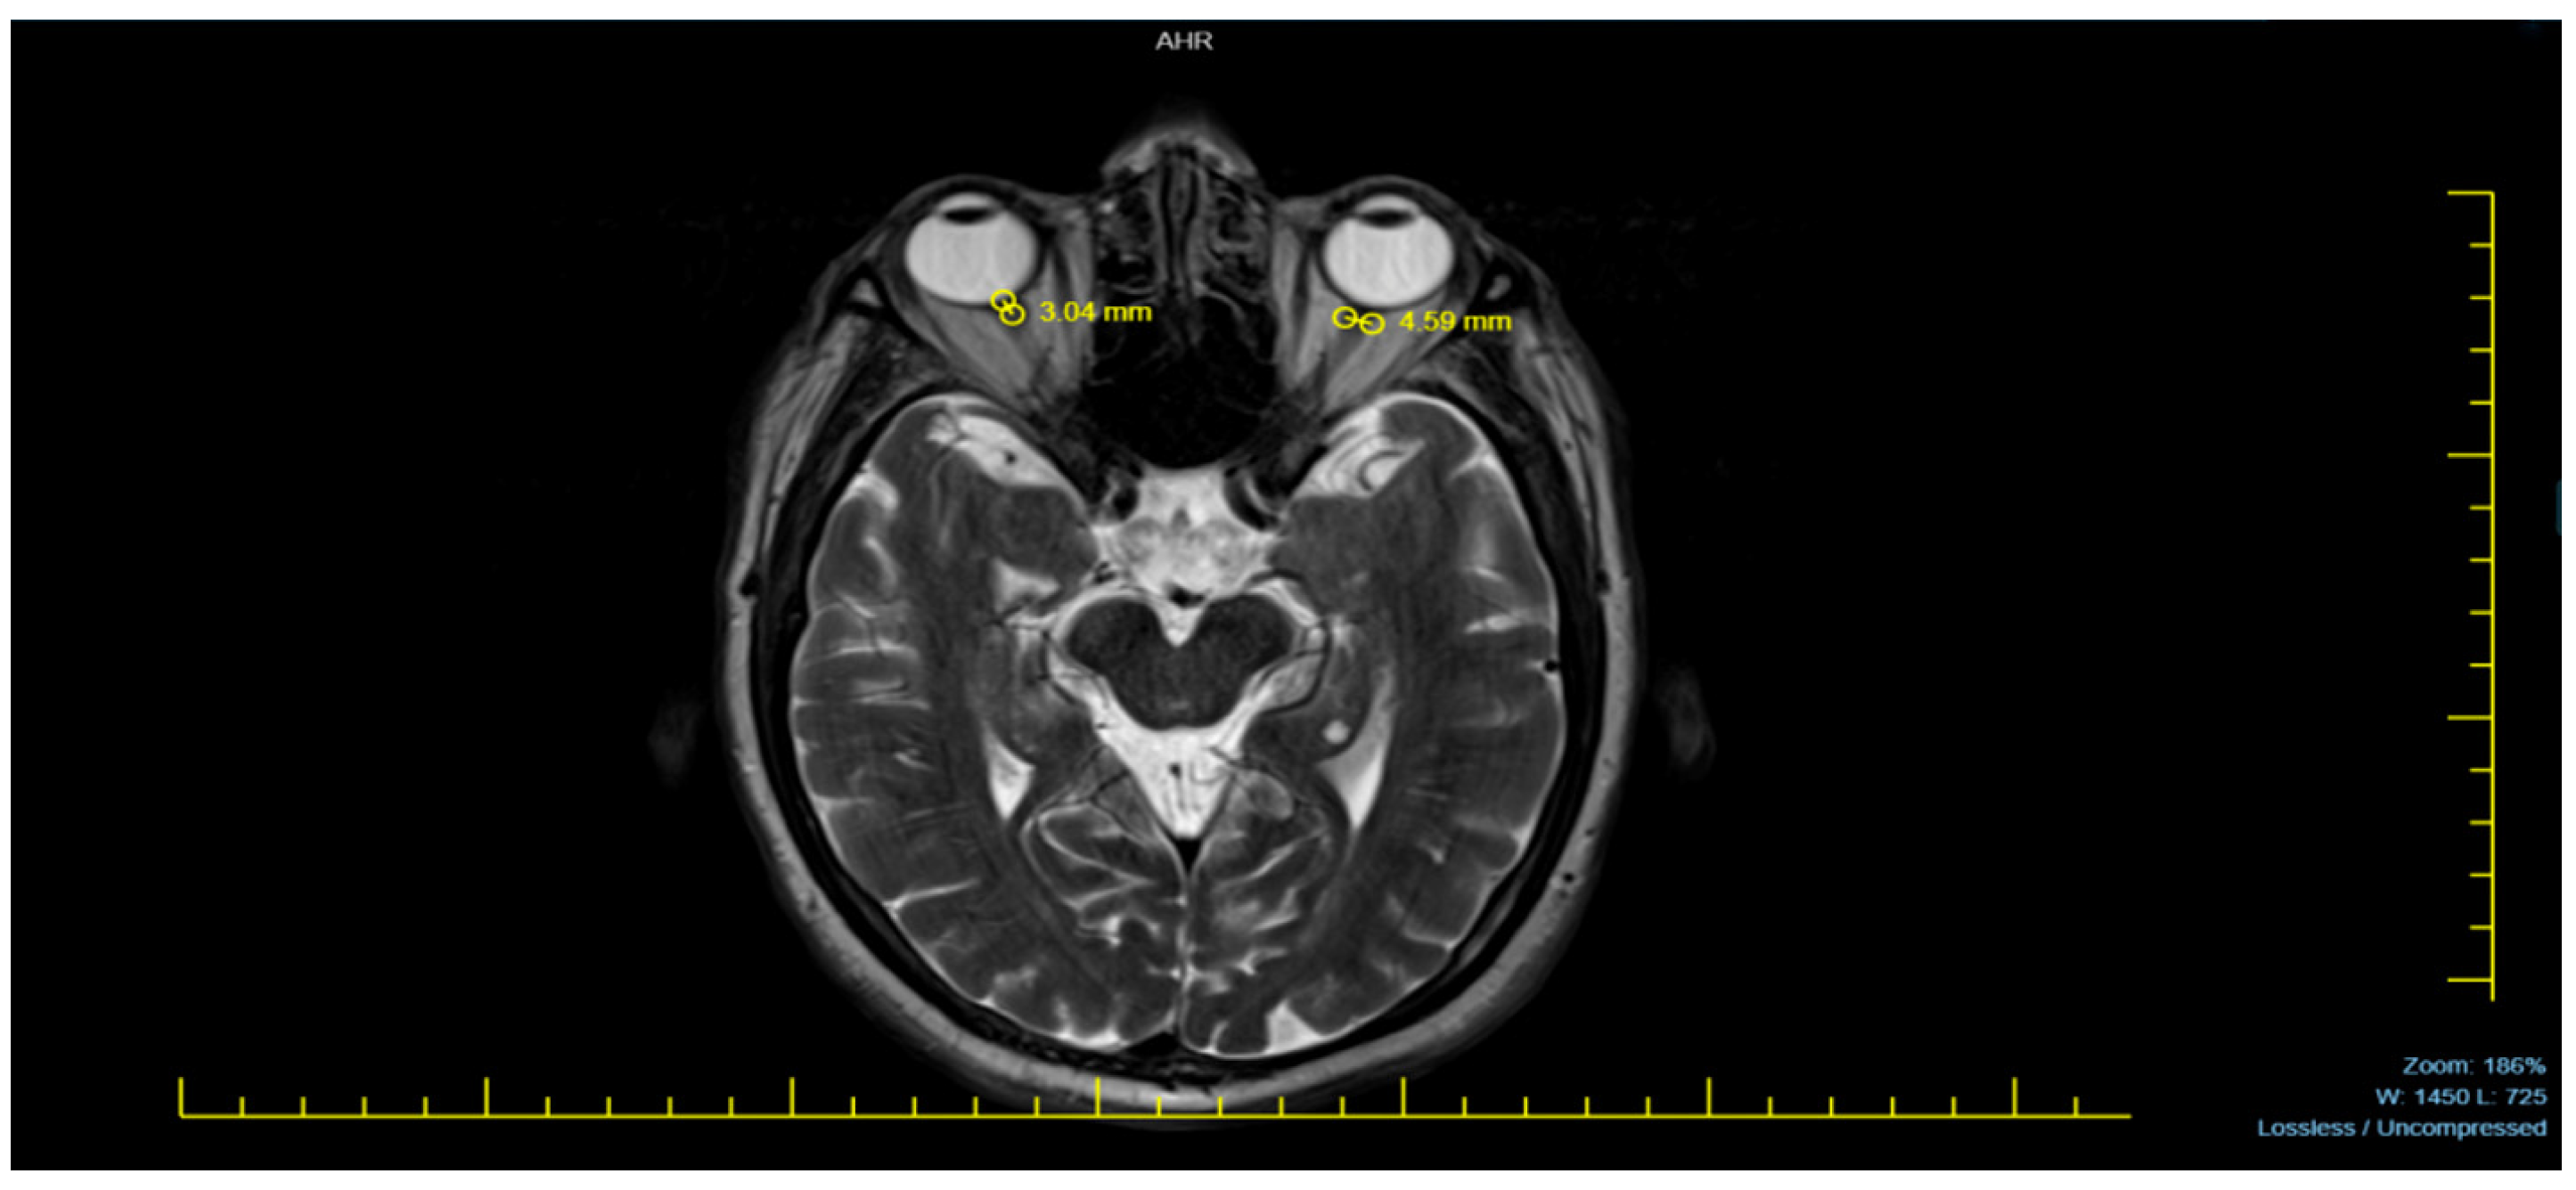

Neurodiagnostic MRI scans were performed using a 1.5 Tesla MRI machine (Siemens Avanto, Erlangen, Germany). The magnetic resonance images of patients were acquired in the T2-weighted axial plane, ensuring optimal visualization of the eyeballs. The ONSD was measured 3 mm posterior to the eyeball, where the optic nerve sheath appeared most distinct. The distance between the dural sheaths, which appeared hypointense adjacent to the hyperintense subarachnoid space surrounding the optic nerve, was measured. To obtain the most accurate result, each measurement was performed three times per eye, and the averages were recorded as a single measurement for each eye [9,10].

Figure 1 provides a representative MRI sample used in measuring the ONSD, illustrating the method applied in this study.

Figure 1. A sample of an MRI.